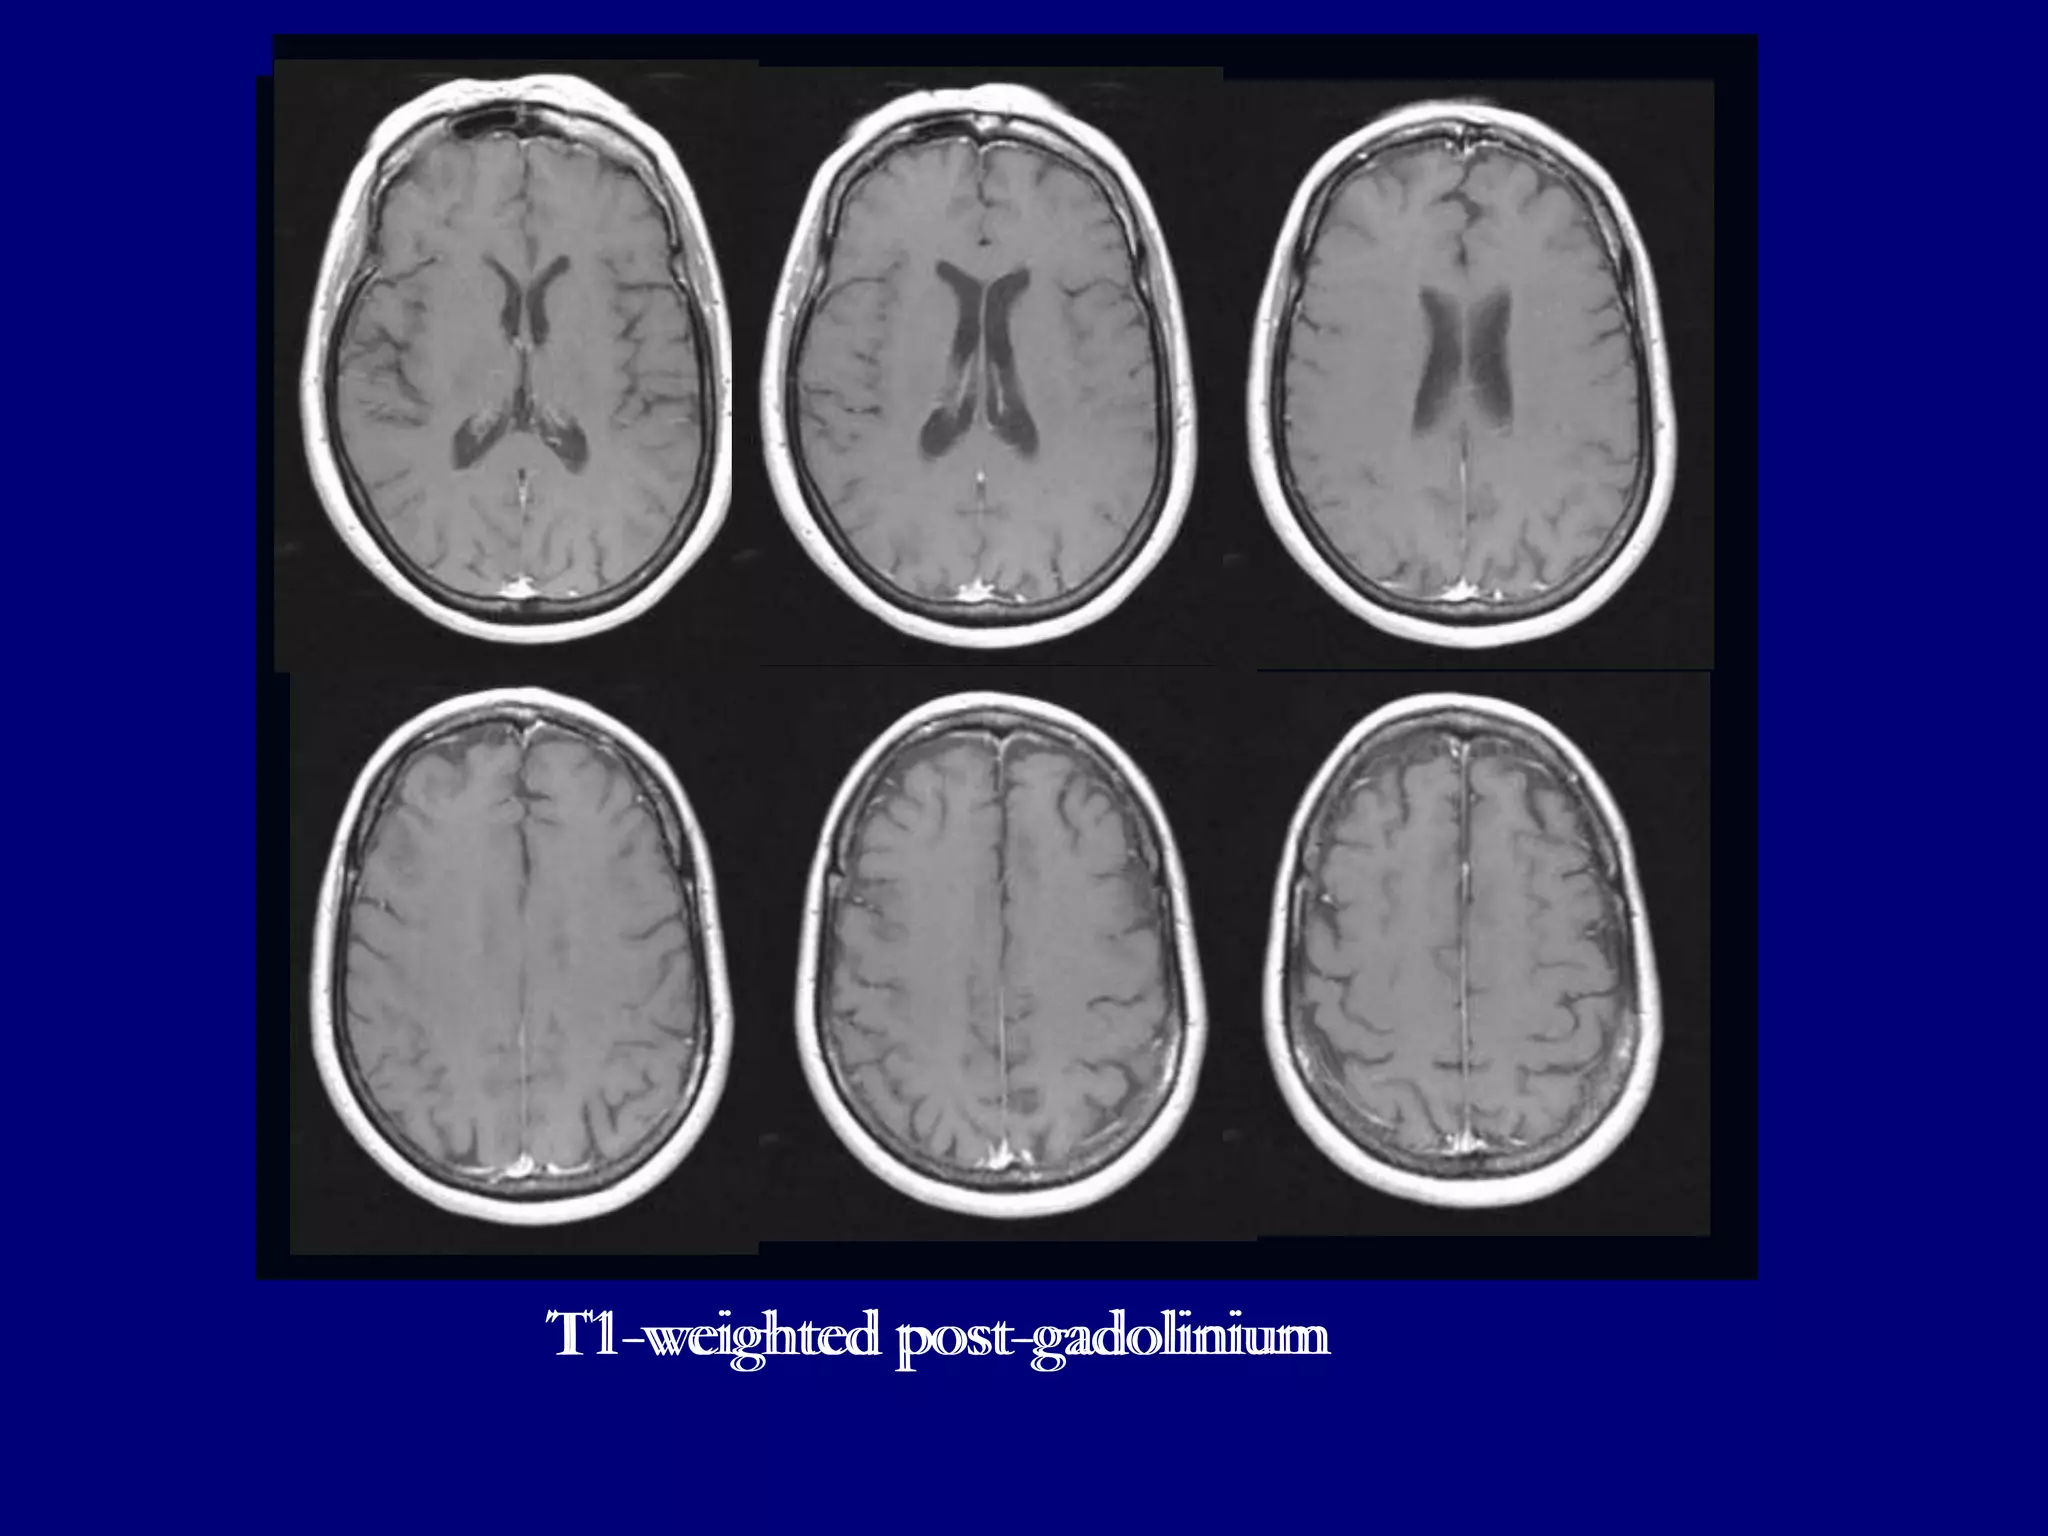

T1-weighted Post-gadolinium images show homogenously enhancing well defined

lesions in left fronto-parietal lobes and enhancement in left cerebellum